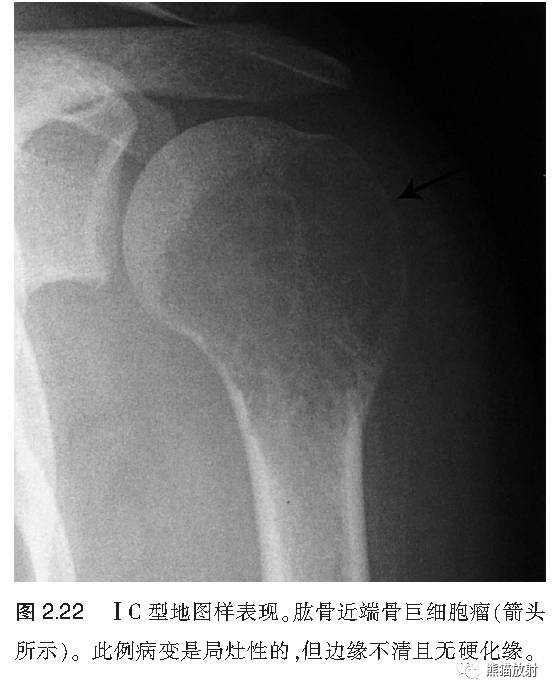

↓ 肱骨近端骨巨细胞瘤

I C:地图样、边缘不清